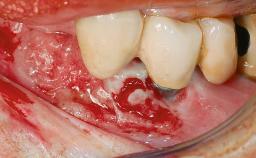

Peripheral Giant-cell Granuloma Associated with Peri-implant Tissues

Giant-cell granulomas (GCG) of the jaws are benign reactive lesions of unknown etiology, unrelated to giant-cell tumors (osteoclastomas), which are defined as benign but locally destructive and aggressive neoplasms (Jundt and coworkers 2005). Depending on their localization at the initial diagnosis, GCG are dived into central (CGCG) and peripheral (PGCG) types. CGCGs occur within the jawbones and appear as unilocular or multilocular radiolucent lesions. The incidence in the general population is very low. They are more commonly found in the mandible, mainly in children and young adults—patients are generally younger than 30 years—and have a greater incidence in females (Heithersay and coworkers 2002). The clinical behavior of CGCGs varies from slowly growing asymptomatic swellings to aggressive lesions that may result in pain, cortical perforation of the affected jaw site, and root resorption (de Lange and coworkers 2007).

Jaw Mandible

Area Anterior|Posterior